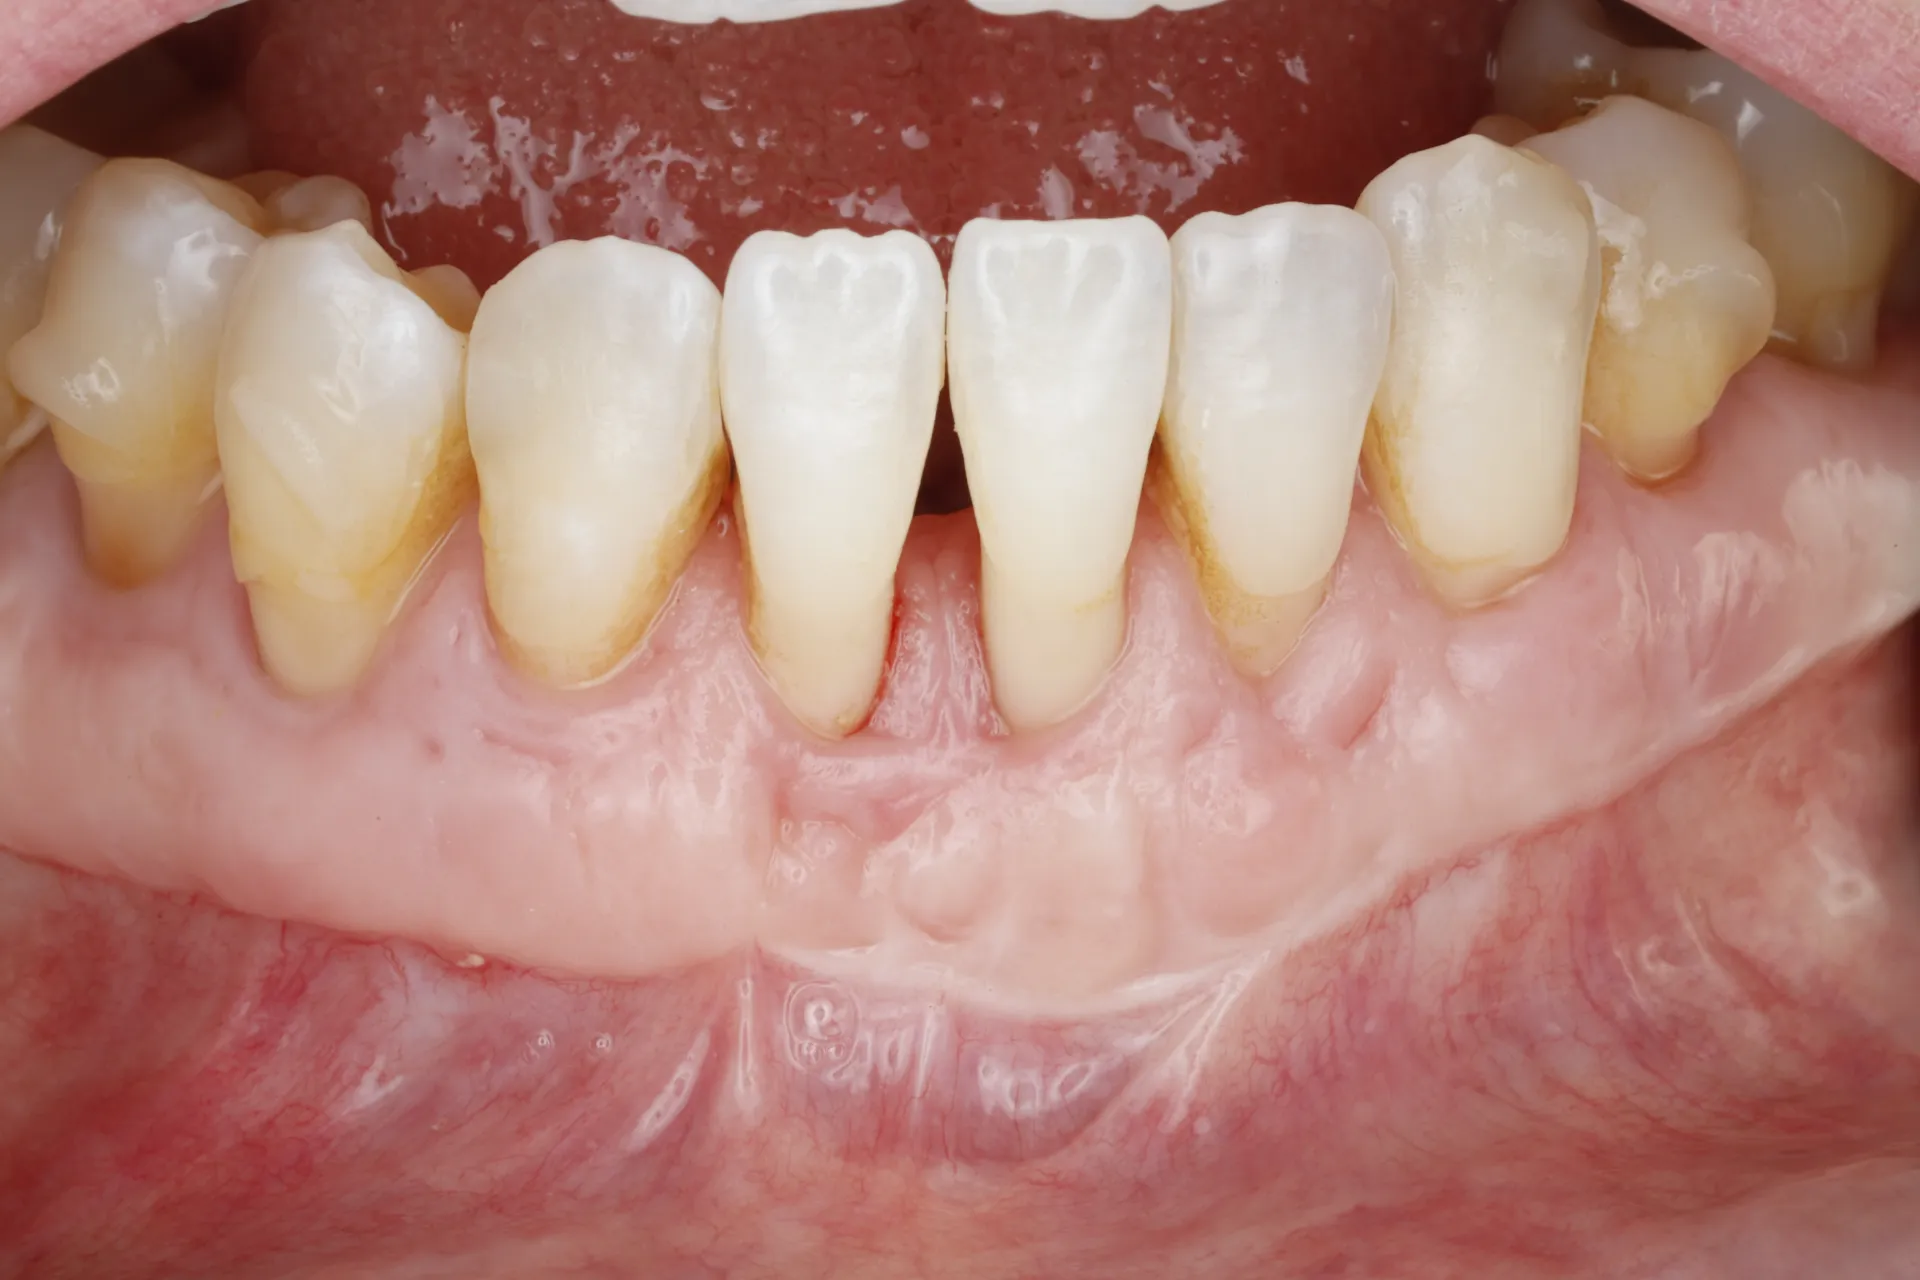

Gum Recession

Gum Grafting